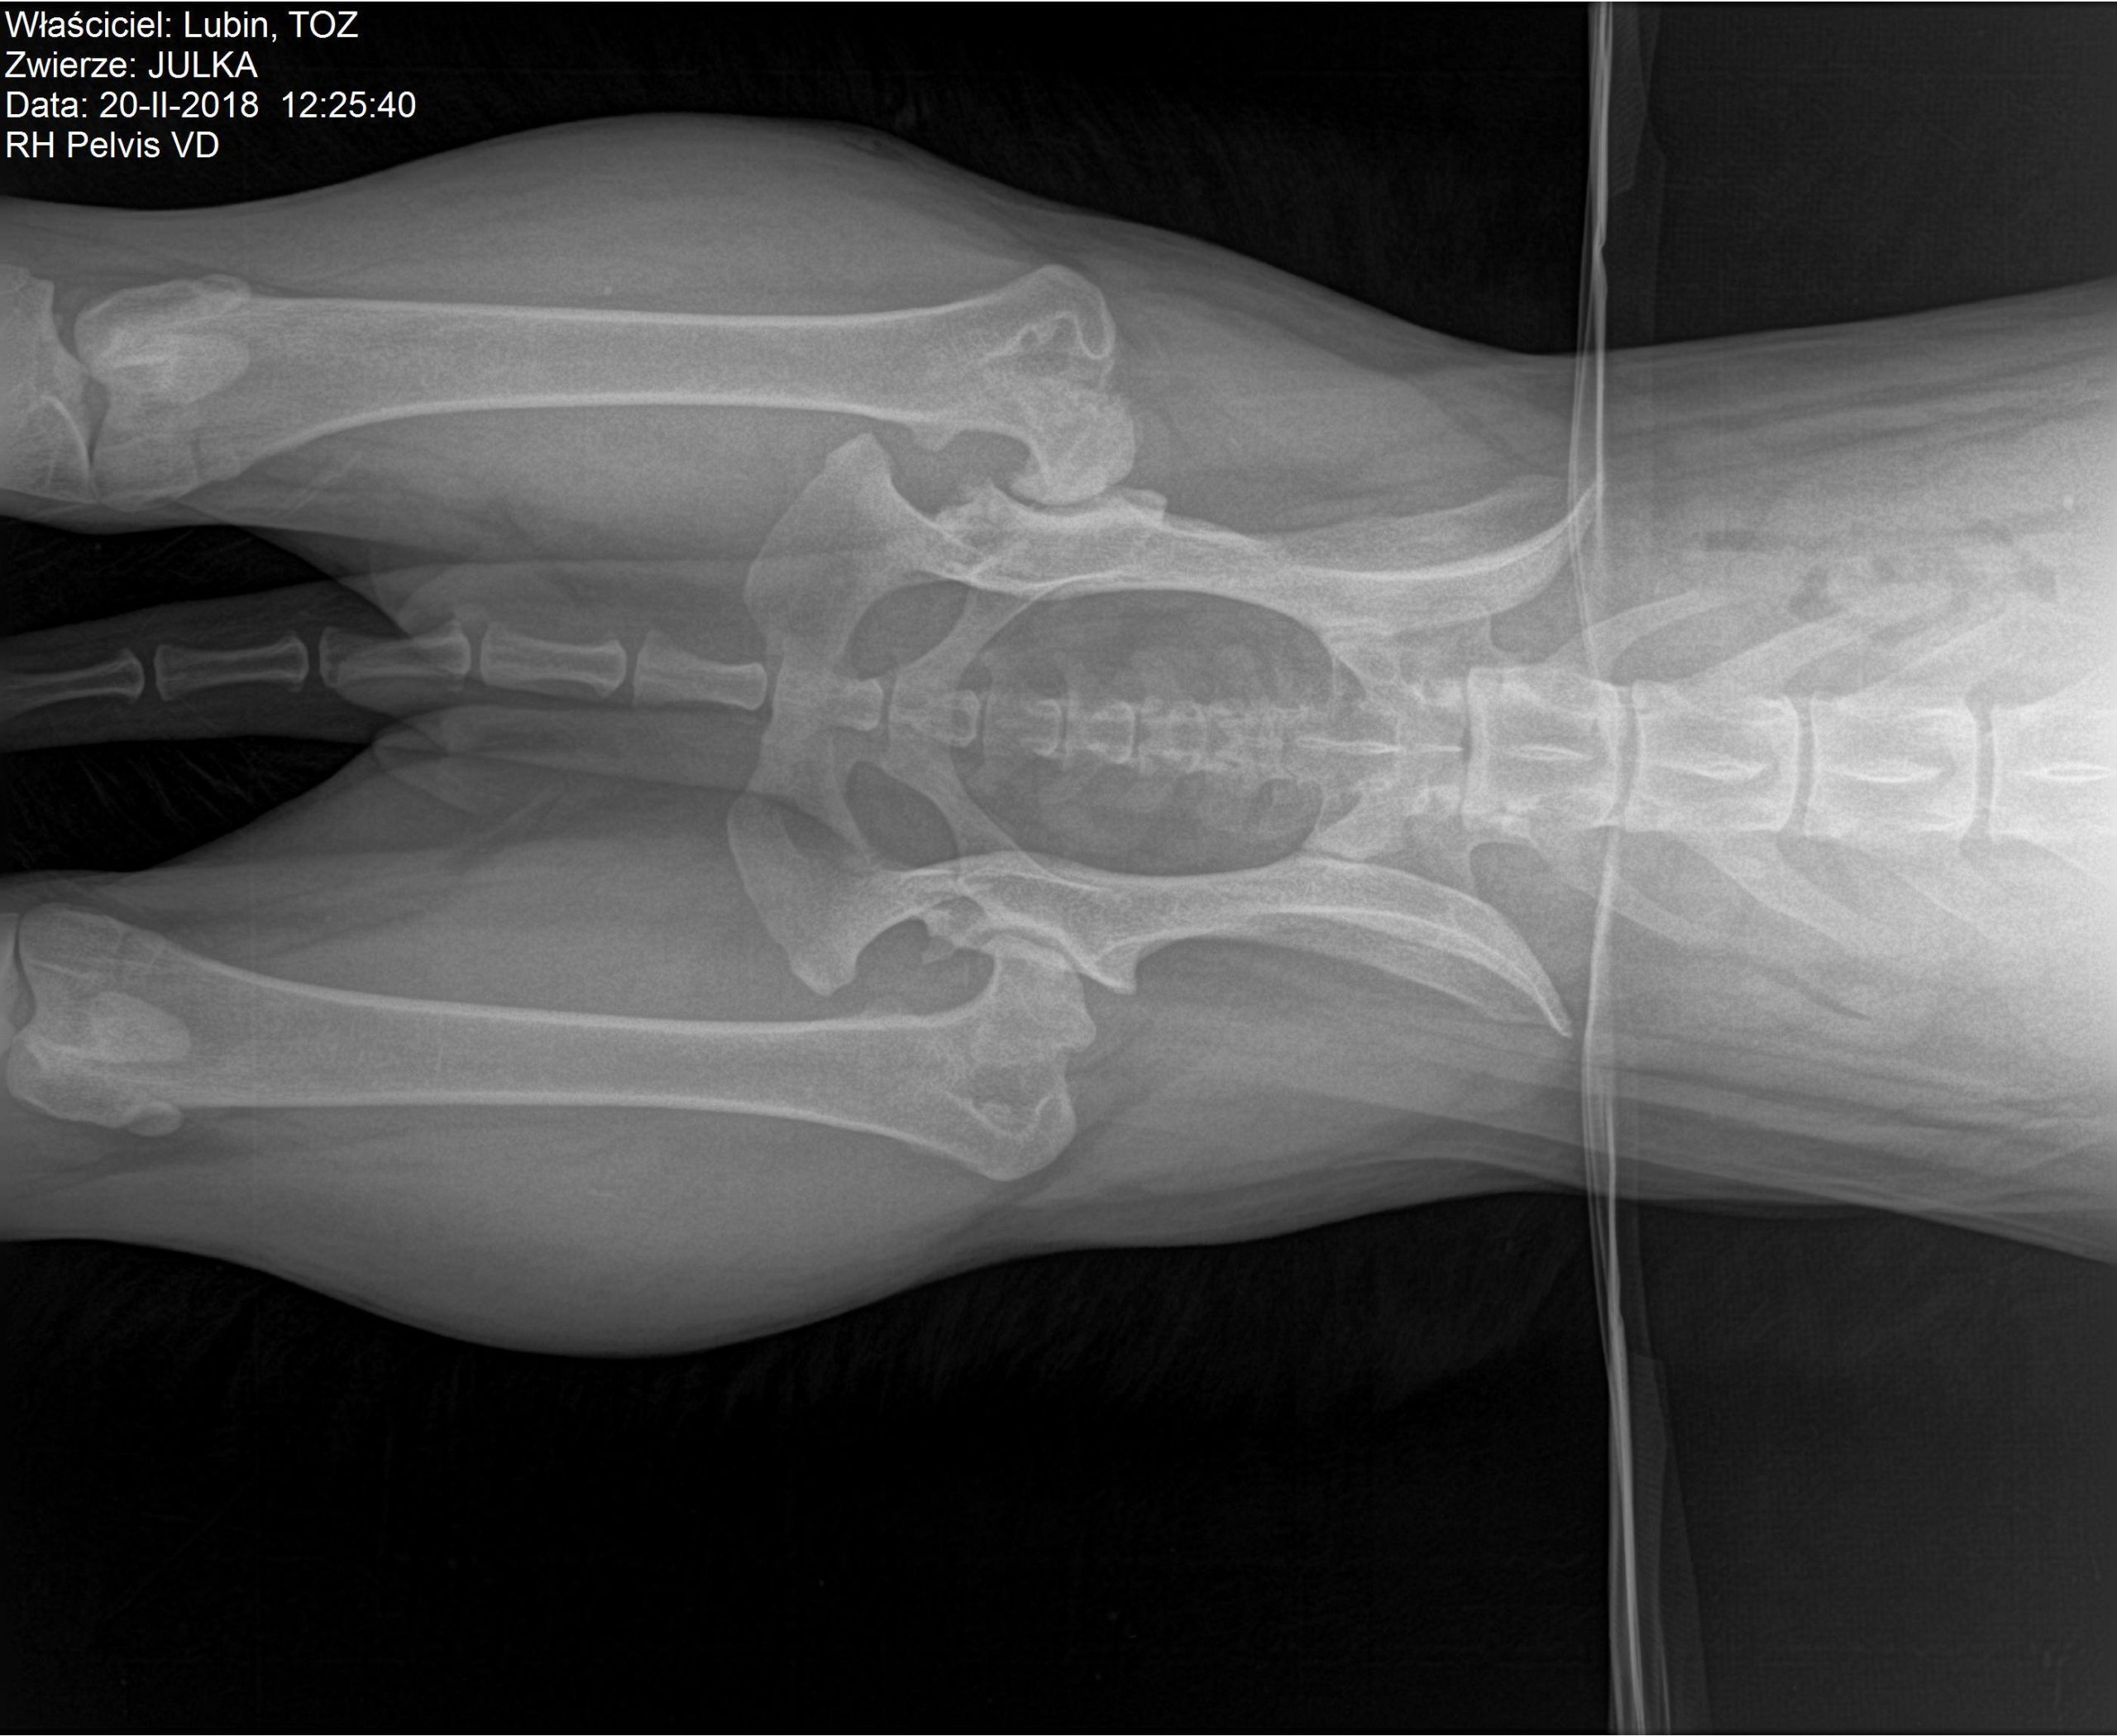

Wracamy do znanej czytelnikom Julki. TOZ ponownie zbiera fundusze na pomoc dla suczki. Julka żyje w ciągłym bólu – problemy z biodrami utrudniają jej bieganie i skakanie. U psiaka zdiagnozowano bowiem dysplazję stawów biodrowych. Dodatkowo ma silną anemię i szybko traci na wadze. Początkowo planowano przeprowadzenie operacji, ale teraz nadarzyła się inna szansa na odzyskanie zdrowia – syntetyczna wiskoproteza.

Niestety stan zdrowia suczki od początku był zły. Julka wymagała długiego procesu leczenia i opieki profesjonalistów. Na początku 2017 r. trafiła do hoteliku w Warszawie, gdzie miała mieć zapewnioną opiekę behawioralną oraz weterynaryjną. Tam zdiagnozowano u suczki ciężką dysplazję stawów biodrowych oraz bardzo silną anemię.

– Julka dziś jest piękną, łagodną 25-kilogramową kuleczką. Jej wdzięczność za nowe życie powala na kolana. Suczka odzyskała równowagę emocjonalną, ale wciąż przeszkodą są problemy natury fizycznej. Dysplazja stawów biodrowych utrudnia suni bieganie, skakanie i inne czynności. Wcześniej sądziliśmy, że będzie musiała przejść operację. Teraz znaleźliśmy nowe rozwiązanie – opowiada Karolina Lorenc.

Pomoc dla Julki czeka na nią w Gdańsku lub bliżej – we Wrocławiu. Nowa metoda Noltrex to syntetyczna wiskoproteza o właściwościach podobnych do mazi stawowej. Jej bardzo wysoka gęstość wspomaga amortyzacją stawu, zapobiegając otarciom, niwelując ból, a zawarte w niej jony srebra działają bakteriostatycznie. Wiskoproteza pomaga zachować integralność chrząstki stawowej, co jest szczególnie istotne w przewlekłych chorobach zwyrodnieniowych.